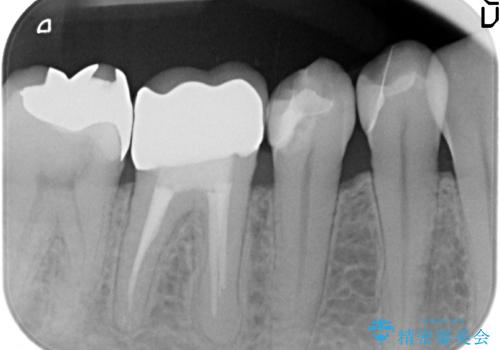

- 奥歯のかぶせものが取れたのと、手前の歯の虫歯治療を希望して来院。

奥歯は神経の治療からやり直し、セラミッククラウンとしました。

手前の歯は1本は虫歯、もう一本もつめものが取れたままでしたので、セラミックインレーとしました。

大臼歯の再根管治療は横浜桜木町歯科院長 大元先生が担当しました。

- 40万円 内訳:右下6(再根管治療13万円、ジルコニアクラウン10万円、ファイバーコア2万円、仮歯1万円)、右下45(セラミックインレー7万円x2本)費用は治療当時の料金となります

右下6番は、歯肉縁下カリエスではなかったため、そのまま補綴することが可能でした。